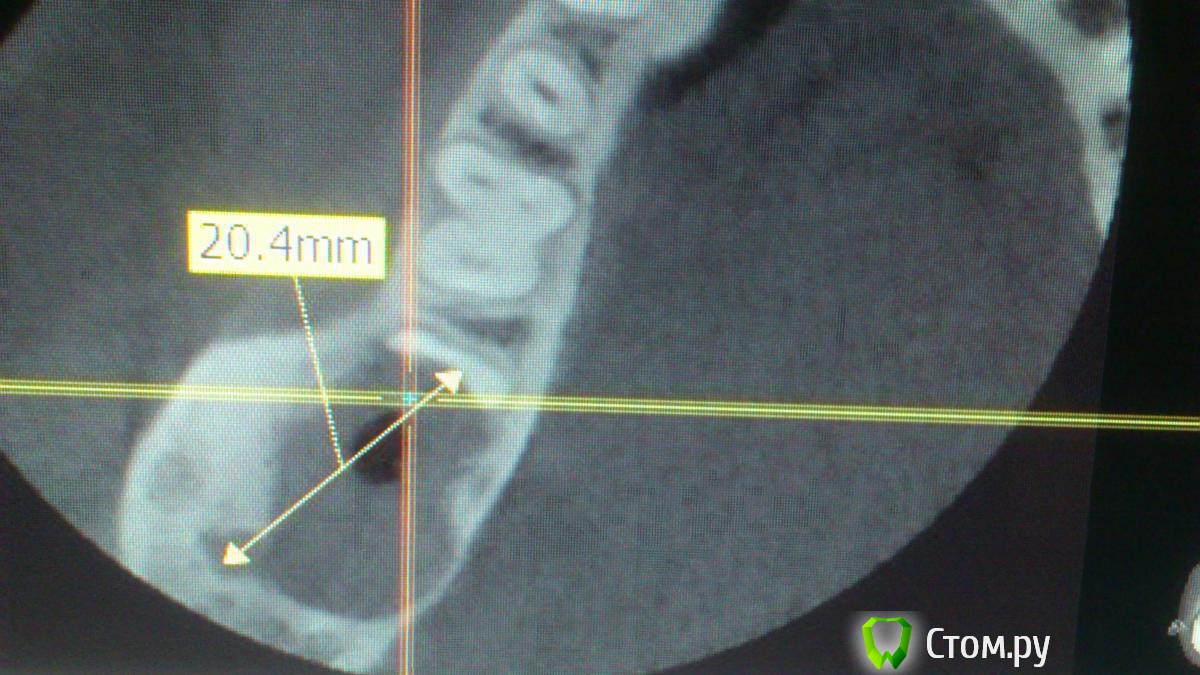

Larnary Опубликовано 17 ноября, 2014 Поделиться Опубликовано 17 ноября, 2014 (изменено) Пришёл на консутацию пациент с КТ. Вижу крупное кистозное образовамие в области 47 и отсутствующего 48.Со слов пациента 48 не было никогда. Отмечаетя полная резорбция корней 47. Сделал принтскрин и направил к онкологу.Пациент обещал позвонить и сообщить результаты Изменено 17 ноября, 2014 пользователем Larnary Ссылка на комментарий

Larnary Опубликовано 17 ноября, 2014 Автор Поделиться Опубликовано 17 ноября, 2014 Да.потпу и направил к онкологу,тк. сильнейшая резорбция корней. думаю круто для кисты. но и полость кисты однородна по структуре Ссылка на комментарий

PLAY Опубликовано 17 ноября, 2014 Поделиться Опубликовано 17 ноября, 2014 А с чего вы взяли, что они резорбированы? Срез сделан неправильно, имхо. Орто надо. я вижу на 2х срезах предоставленной кт-резорбцию корней. фолликулярная киста проходит через эмалево-цементную границу, тут образование, просто отхапало пол-зуба, линия новообразования неравномерная, меня бы это насторожило Ссылка на комментарий

Larnary Опубликовано 17 ноября, 2014 Автор Поделиться Опубликовано 17 ноября, 2014 врачи потому и направили на КТ,тк на панораме нет корней.только краешек медиального корня. да и я кт вертел. нет их там Ссылка на комментарий

Larnary Опубликовано 17 ноября, 2014 Автор Поделиться Опубликовано 17 ноября, 2014 увеличил нижний кадр Ссылка на комментарий